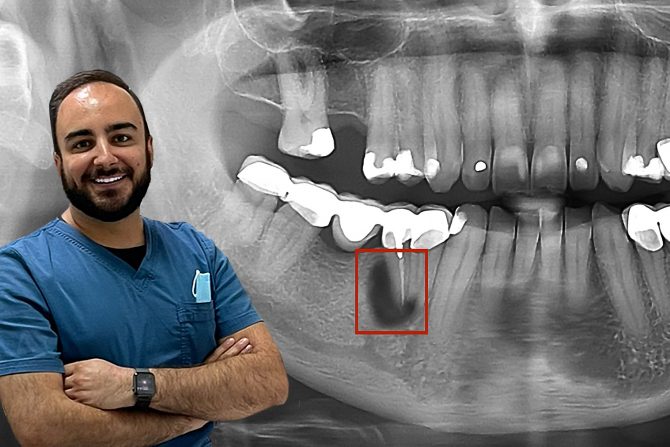

Gangrena zuba, lečenje Proces lečenja gangrene zuba Foto: en.webdento.com

- Najčešće je neophodna višenedeljna, nekada i višemesečna terapija koja podrazumeva, narodski rečeno „vađenje gangrenozno promenjenog živca“, čišćenje kanala korena zuba od naseljenih bakterija, primenu medikamenata, i na kraju definitivno „punjenje“ kanala korena zuba, uz adekvatnu restauraciju plombom ili krunicom - objašnjava dr Ivan Stanić.